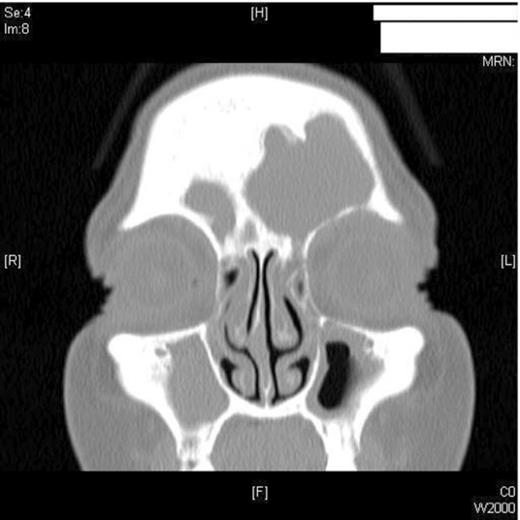

A 47-year old female smoker presented to the ENT department with worsening pain and progressive swelling to her left peri-orbital region and eyelid. On clinical examination the patient was acutely unwell. Rhinoscopy revealed mucopus draining from the left middle meatus. CT scanning revealed severe sinus disease in both frontal sinuses, with the left frontal sinus being expanded suggesting the presence of a mucocele (Figure 1). Both Frontonasal recesses and osteomeatal complexes were seen to be occupied by material bilaterally. Following Opthalmological review, she was managed initially with intravenous antibiotics and systemic steroids as well as intranasal steroids, decongestants and antimicrobial eye ointment. However, due to failure in resolution of symptoms, she was listed for surgical drainage of the mucocele using balloon sinuplasty.